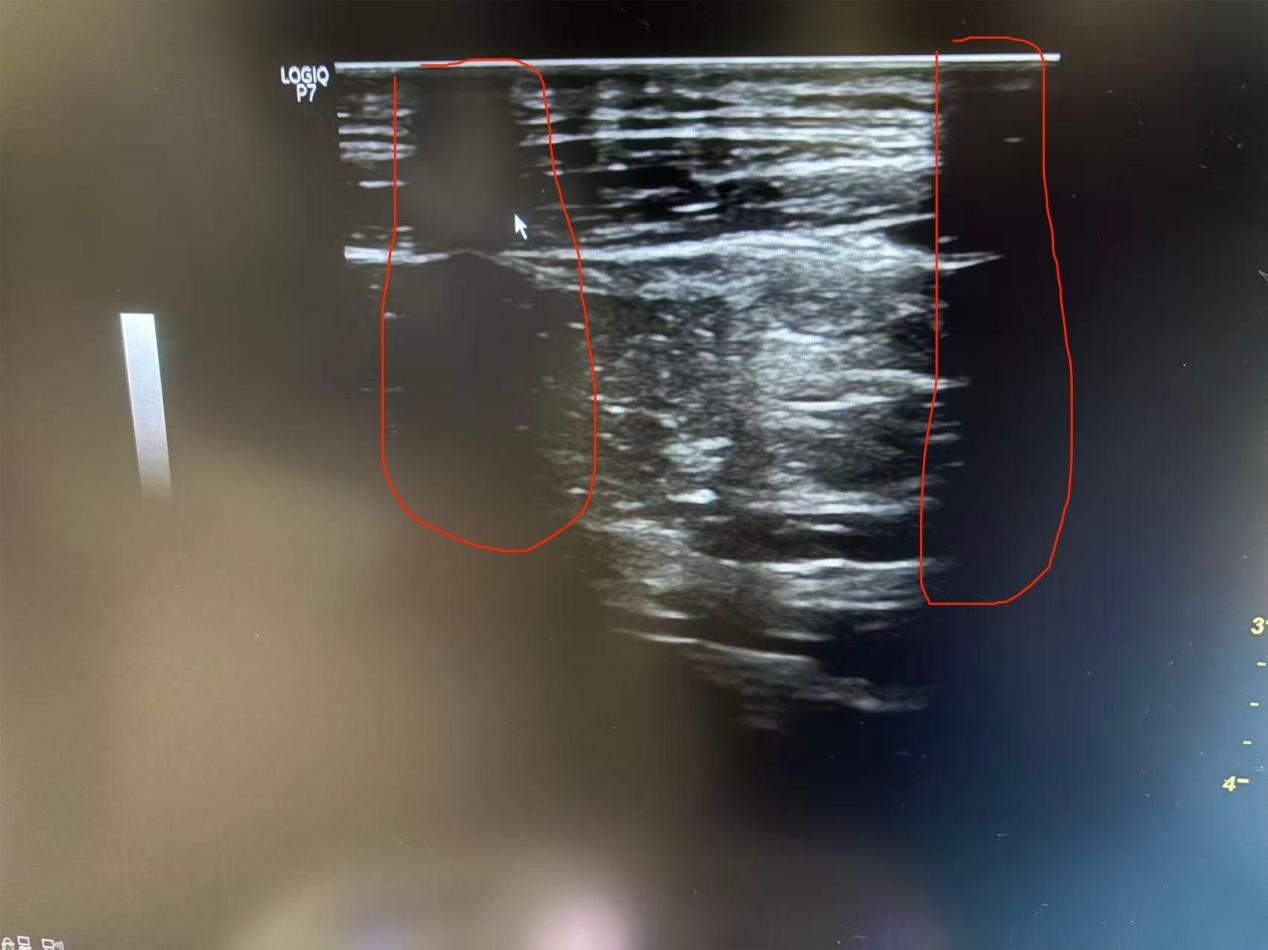

| 設(shè)備型號 | Logiq p7 |

| 故障現(xiàn)象 | 淺表探頭在檢查時(shí)部分區(qū)域無圖像,需更換探頭晶體一套,鍵盤上鎖定按鍵偶爾出現(xiàn)失靈。 |